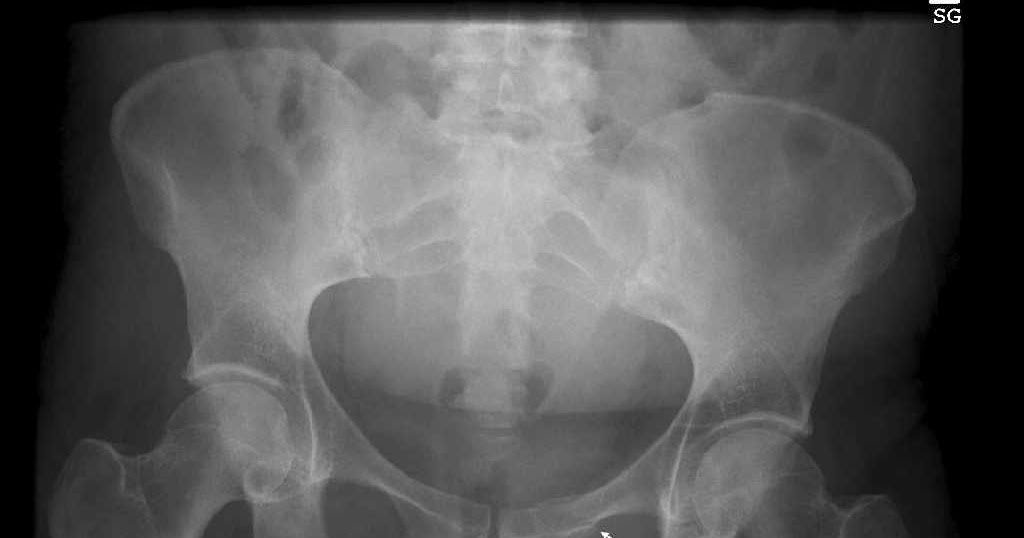

Fractured Inferior Pubic Ramus with Ipsilateral Total Hip ...

Fractured Inferior Pubic Ramus with Ipsilateral Total Hip ... from static-01.hindawi.com

The pubis itself is made up of two smaller bones. I'm so scared because i start running competitively again soon. The pubis, the ischium, and the ilium. Inferior pubic ramus spreads out from the lower as well as lateral part of the body of pubis and on the medial side of the obturator foramen creates ischiopubic… 27193 (closed treatment of pelvic ring fracture, without manipulation). No obvious fracture femoral or pelvic fracture can be observed. Fractures of the pubic rami are nearly always associated with further pelvic ring with more complex, unstable pelvic ring injuries, ramus fractures may require fixation to. If so can you describe what it felt like and if it was op, what you did to resolve? Superior pubic ramus fractures were classified according to a new scheme, the nakatani system, which categorizes superior ramus fractures. Is it possible i fractured it again?! Has anyone been diagnosed with osteitis pubis or a pubic ramus stress fracture? If there is a fracture of one pubic ramus there is almost always a second fracture of the other. The optimal surgical procedure for pubic rami fractures must ensure a stable fixation and simultaneously minimize the risk of postoperative complications. Fractures of the pubic rami are the most frequent osteoporotic pelvic fracture. Pubic rami pubic ramus fracture. The pubis, the ischium, and the ilium. The left and right pubic bones are each made up of three sections, a superior ramus, inferior ramus, and a body.